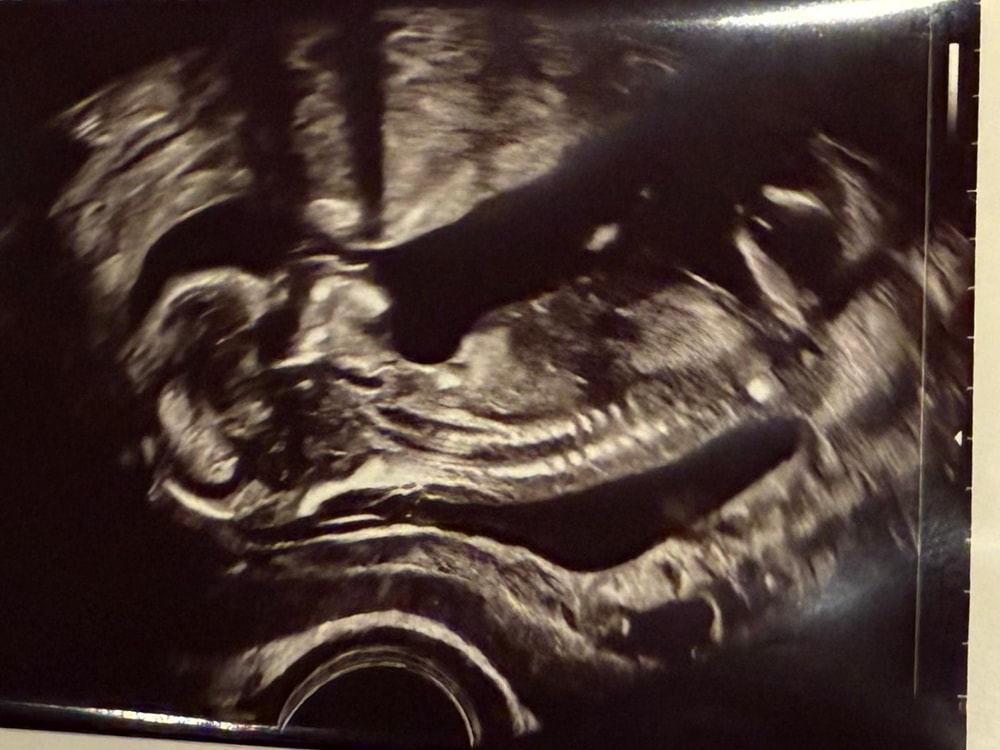

Кого видите?

А то, что у него там что-то торчит, это может совсем не то, о чем вы думаете)) Он слишком маленький еще, чтобы так торчало. Я по полоске смотрю, у девочек вдоль позвоночника идет такая тоненькая полосочка, здесь ее не вижу. Но может ракурс просто неудобный

А мне кажется, что как раз бугорок за ножкой торчит и это девочка. Здоровья🫶🏻

Сейчас такой срок, когда уже по наклону бугорка не понять и органы еще не сформированы, ошибиться ну очень легко. Подождите еще пару недель и будет яснее

Плохо видно, ножкой закрывает

Странно, а я вообще первый раз в жизни увидела совершенно отчётливо мальчика. А Вы кого хотите?))

Петрификус Тоталус, у нас нет предпочтений, но нам тоже показалось, что между ног болтается что-то 😂

Пол ребенка Пол малыша по бугорку